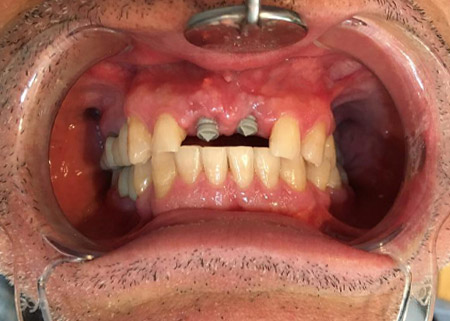

BEFORE & AFTER – IMPLANTS

Dental & Anti-aging treatments will change your life. The end results are astonishing. View some before and after photo of a dental treatment

BEFORE